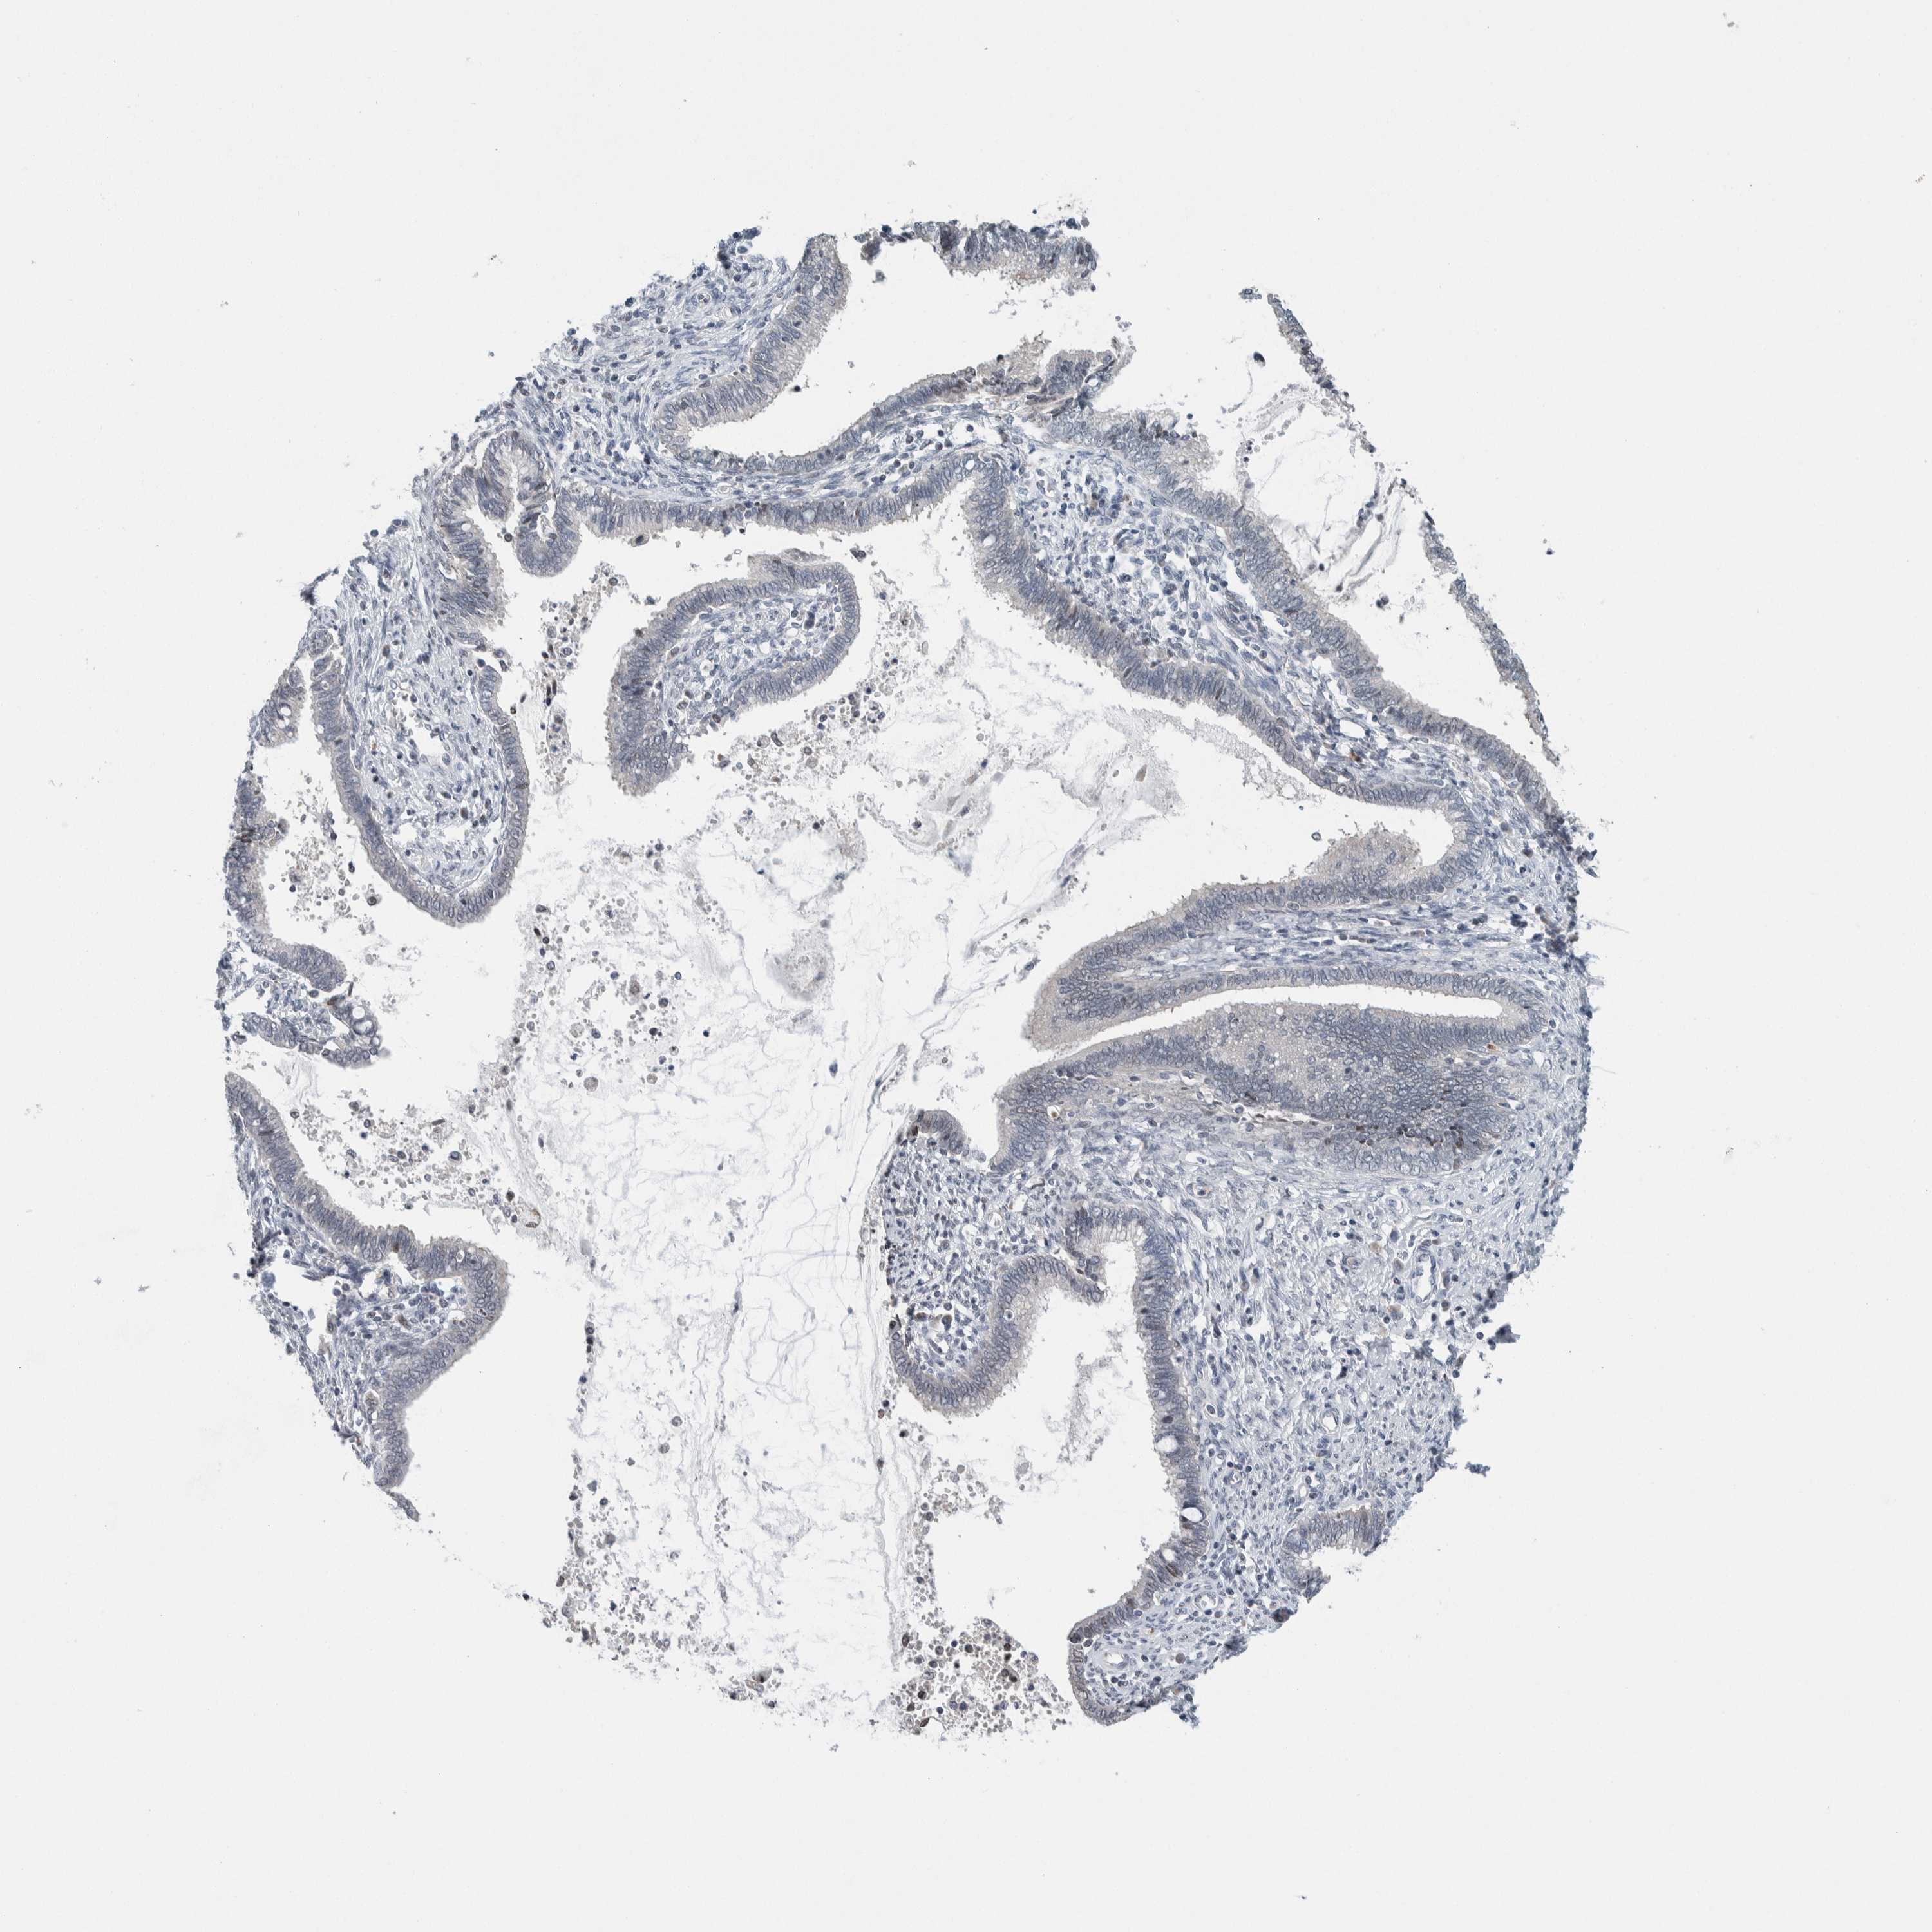

CERVICAL CANCER - Protein expressioni

A mouse-over function shows sample information and annotation data. Click on an image to view it in a full screen mode. Samples can be filtered based on level of antibody staining by selecting one or several of the following categories: high, medium, low and not detected. The assay and annotation is described here.

Note that samples used for immunohistochemistry by the Human Protein Atlas do not correspond to samples in the TCGA dataset.

Antibody stainingi

Antibody staining in the annotated cell types in the current human tissue is reported as not detected, low, medium, or high, based on conventional immunohistochemistry profiling in selected tissues. This score is based on the combination of the staining intensity and fraction of stained cells.

Each image is clickable and will lead to virtual microscopy that enables deeper exploration of all samples and also displays staining intensity scores, fraction scores and subcellular localization as well as patient and tissue information for each sample.

Antibody HPA003278

Antibody CAB022450

Staining

High

Medium

Low

Not detected

Intensity

Strong

Moderate

Weak

Negative

Quantity

>75%

75%-25%

<25%

None

Location

Nuclear

Cytoplasmic/membranous

Cytoplasmic/membranous,nuclear

Squamous cell carcinoma, NOS

Adenocarcinoma, NOS